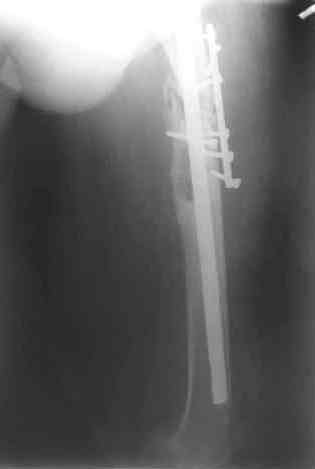

После нескольких некрэктомий, проведения аутодермопластики и заживдения ожоговой раны через 2 месяца после травмы произведен открытый остеосинтез левой бедренной кости штифтом и пластиной (деротационной) [image 01, 02]. Через 1 год и 7 месяцев после травмы у больного диагностированы ложный сустав и хронический остеомиелит левой бедренной кости. Произведено удаление металлических фиксаторов, секвестрэктомия и остеосинтез бедренной костивнешним двухплоскостным стержневым аппаратом [image 03, 04] .

Через 3 года после травмы констатировало отсутствие консолидации бедренной кости, сохранение признаков хронического остеомиелита (свищ в нижней трети левого бедра). Произведен демонтаж аппарата, реостеосинтез бедренной кости спице-стержневым аппаратом, некрсеквестрэктомия. В аппарате удалось лишь частично произвестиустранение углообразной деформации бедренной кости [image 05] .